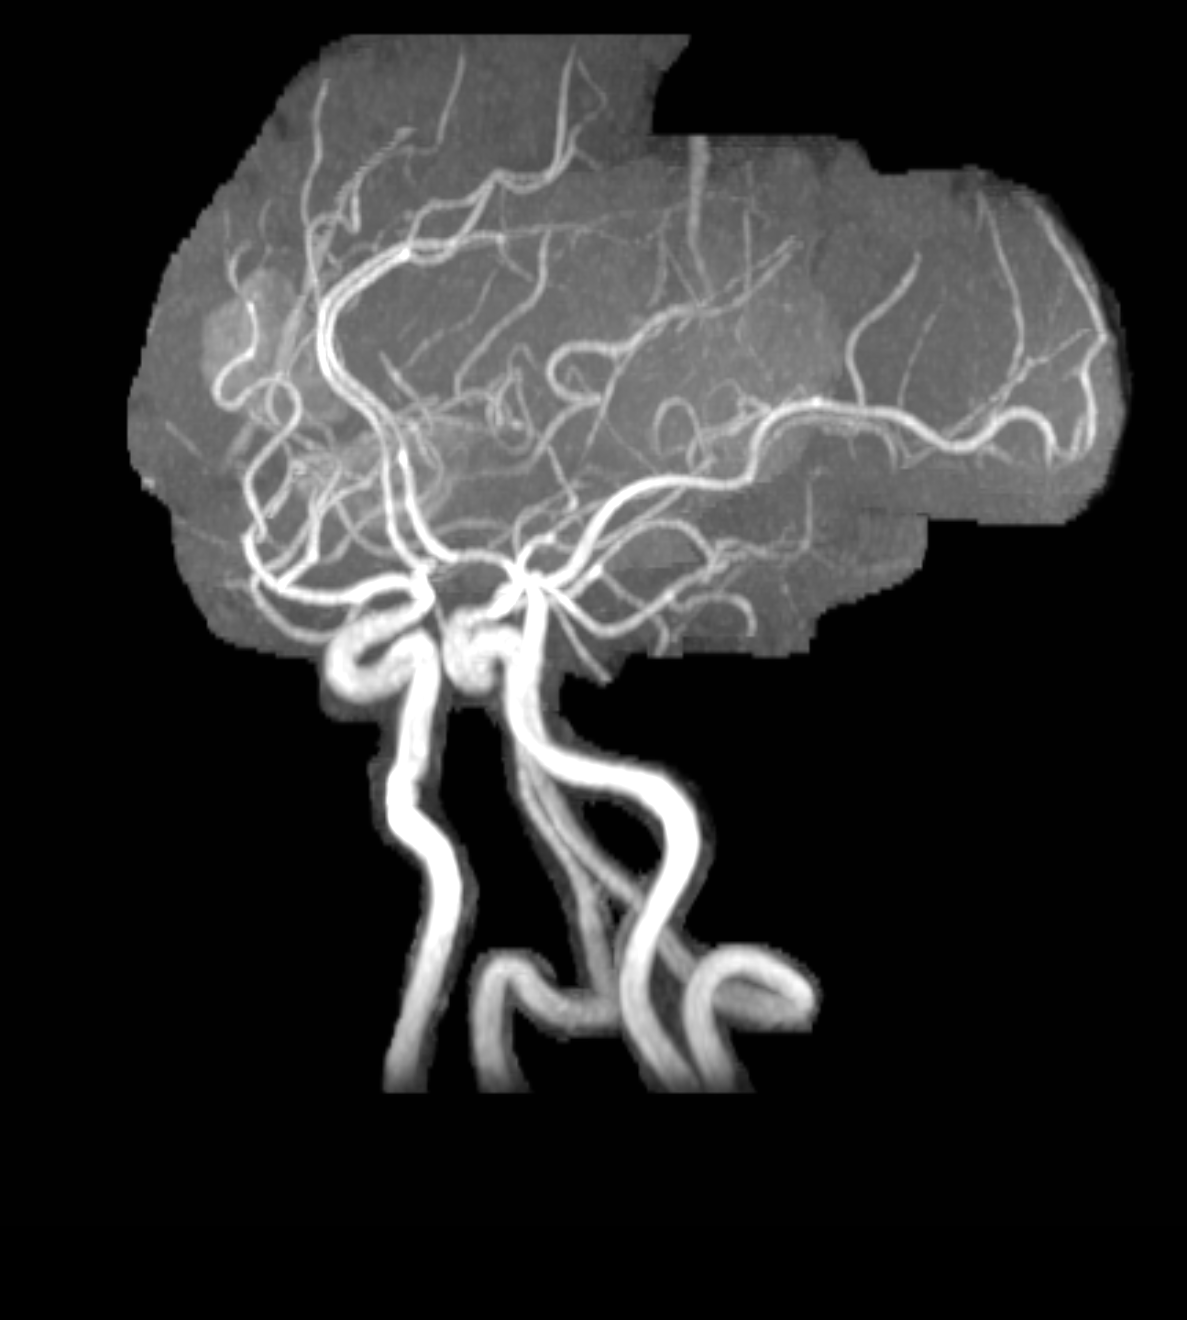

Case Presentation: : A 34-year-old female with history of migrainous headaches presented with complains of sudden onset, throbbing type of headache radiating to the back of the ear. This was associated with sudden loss of vision in the right eye. She also mentioned night sweats and unintentional weight loss in the last couple of months. She was diagnosed with grade 1 neuroendocrine tumor three months ago. On examination, she exhibited tenderness over the right temporal area and a decrease in visual acuity on the right eye. She did not show any signs of other focal neurological deficits. Initial laboratory investigations revealed thrombocytopenia and an elevated erythrocyte sediment rate. She was empirically treated with high dose glucocorticoids. Computed tomography (CT) scan of brain without contrast did not show evidence of intracranial hemorrhage. However, there were low density areas in the right frontal and temporal lobes suggesting possible demyelinating diseases, infarcts or metastasis. The patient was treated with high dose prednisone, which improved her visual acuity. This led us to do bilateral temporal artery biopsy which was negative for temporal arteritis. Magnetic resonance imaging (MRI) of the brain showed hemorrhagic areas which suggested the possibility of hemorrhagic intracranial metastatic disease, septic emboli or CNS vasculitis. Septic embolism was a distinct consideration, though this was excluded by negative transthoracic echocardiogram and blood cultures. The incidence of metastatic grade 1 neuroendocrine tumor is rare and seemed unlikely. We then proceeded to evaluate for vasculitis. Anti-nuclear antibody titers were highly positive as was Anti- double stranded DNA antibody. Complement 3 and 4 were low. Her presentation was consistent with SLE. On the next step, MR angiogram of brain confirmed small vessel hemorrhage in the right frontotemporal lobe suggestive of CNS vasculitis. High dose prednisone was continued for two weeks and a follow up MRI of brain showed improvement in the hemorrhagic areas. We concluded that the patient was suffering from CNS vasculitis secondary to SLE.